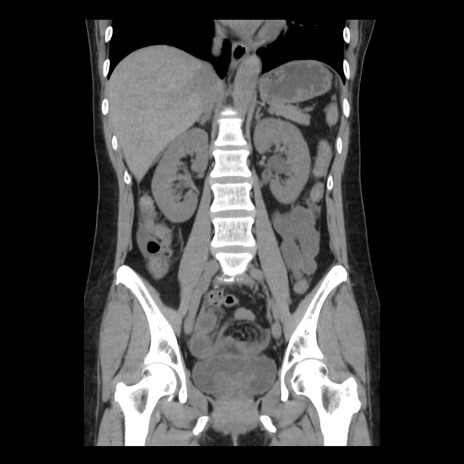

症例10(冠状断像)

【症例】 50歳代女性

【主訴】 腹痛

【現病歴】前日生レバーを食べた。今朝に排便あり。 昼前に突然発症の腹痛を生じ、当院救急外来を受診した。

【既往歴】 子宮筋腫にてで子宮全摘後

【身体所見】 意識清明、腹部:平坦、軟、下腹部やや左を中心に圧痛・反跳痛あり、筋性防御あり

【データ】WBC 7800、CRP 0.07